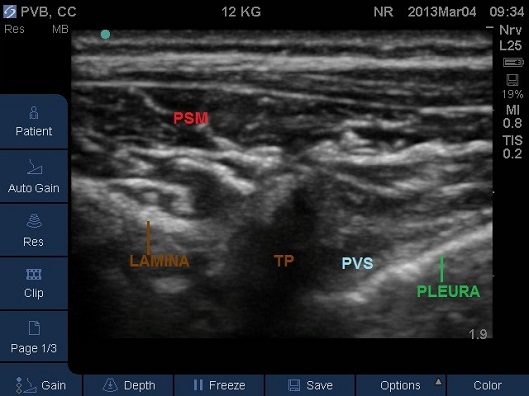

Fig 8. Transverse Plane Mid-Thoracic level. PSM – paraspinal muscles, PVS – paravertebral space, SP – spinous process, TP –transverse process.

- Identify the rib and intercostal muscles lateral to the transverse process (Fig 9).

Fig 9. Transverse Plane Mid-Thoracic level. PSM – paraspinal muscles, TP – tip of transverse process